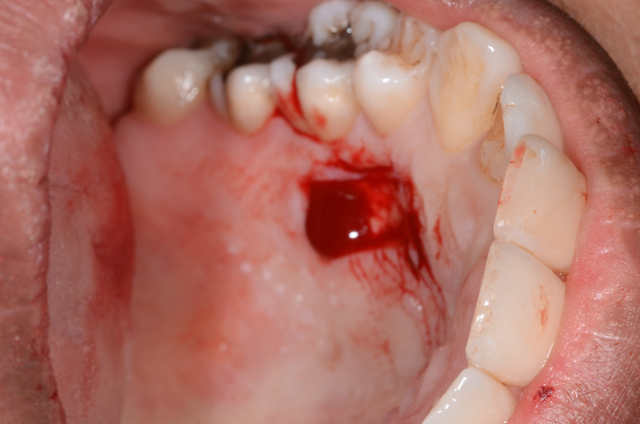

Voila, c`est ma deuxième GGL. Il y avait 0.5mm de gencive attachée sur la 41. On voit la cicatrisation à 48 heures.